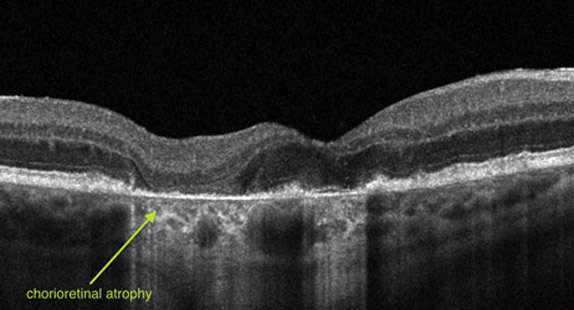

EARLY AMD

INTERMEDIATE AMD

LATE AMD

In neovascular AMD, also called WET AMD, abnormal blood vessels grow underneath the retina. These vessels can leak fluid and blood, which may lead to swelling and damage of the macula. The damage may be rapid and severe, unlike the more gradual course of Dry AMD. It is possible to have both DRY and WET AMD in the same eye, and either condition can appear first.